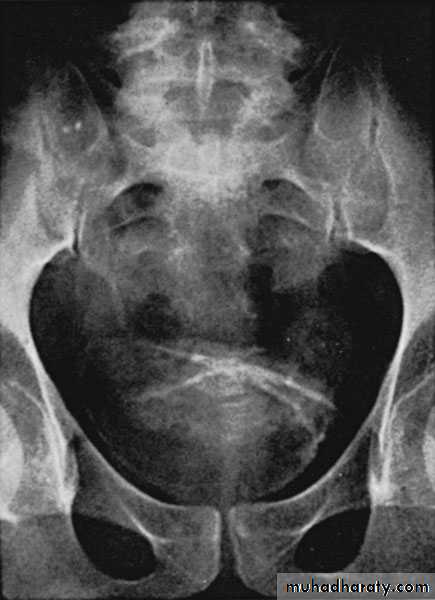

KUB: Renal calcification

IVU

Imaging study

KUB